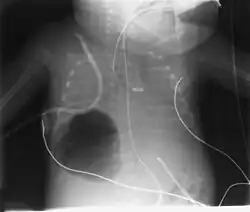

Diagnosis can be made using chest X-ray; the lesion shows up as a small, round area filled with air.[1] Computed tomography can give a more detailed understanding of the lesion.[1] Differential diagnoses – other conditions that could cause similar symptoms as pneumatocele include lung cancer, tuberculosis,[7] and a lung abscess[1] in the setting of hyper IgE syndrome (aka Job's syndrome), as a complication of COVID-19 pneumonitis,[8] or on its own, often caused by Staphylococcus aureus infection during cystic fibrosis.